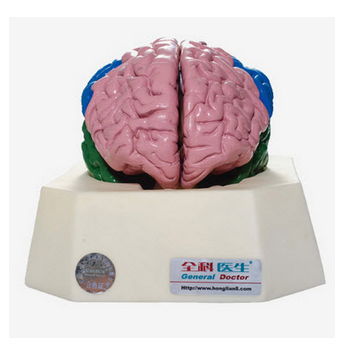

大腦分葉模型 GD/A18204功能介紹:■ 尺寸:自然尺寸■ 材質(zhì):進口PVC材料、進口油漆模型置于基板上,可分解成8部分,包括大腦半球、小腦和腦干等。著色顯示大腦皮質(zhì)分葉。共顯示6個部位 1 額...